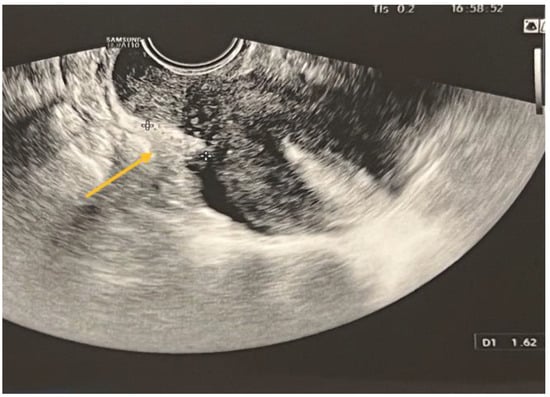

In the case of rectal endometriosis, the specificity of TVS was shown to be lower compared to MRI, with values of 76.87% and 94.51%, respectively. The sensitivity of TVS and MRI exhibited a similar level of comparability, with values of 69.72% and 66.28%, respectively. The diagnostic accuracies of the two procedures were found to be similar and statistically significant. For TVS, the accuracy was 73.82% (Cohen’s κ = 0.46, p < 0.001), while for MRI, the accuracy was 80.79% (Cohen’s κ = 0.61, p < 0.001). Among a total of 256 patients, 109 individuals exhibited rectal endometriotic nodules, leading to the implementation of surgical procedures. Specifically, rectal shaving was performed in 5.5% of cases, discoidal resection in 1.84% of cases, and end-to-end anastomosis segmental resection in 92.66% of cases.

TVS is employed to diagnose bowel DIE by recognizing the thickening of the intestinal wall in a solid or plaque-like approach, as well as the absence of visceral fat separating the recto-sigmoid and the uterine wall [17,18]. The findings are depicted in Figure 6, where the yellow arrow highlights the existence of a rectal nodule exhibiting a negative “sliding sign” and the asterisks indicate the length of the lesion. This sign denotes the absence of rectal mobility in relation to the uterus and the posterior vaginal fornix, suggesting the likelihood of adhesion and endometriosis lesions [17,18]. The adherence of the rectal DIE nodule to the uterine torus is illustrated in Figure 6B.

Figure 6. (A) TVS aspect of rectal endometriosis lesion, (B) TVS aspect of rectal endometriosis lesion adherent to uterine torus endometriosis lesion.